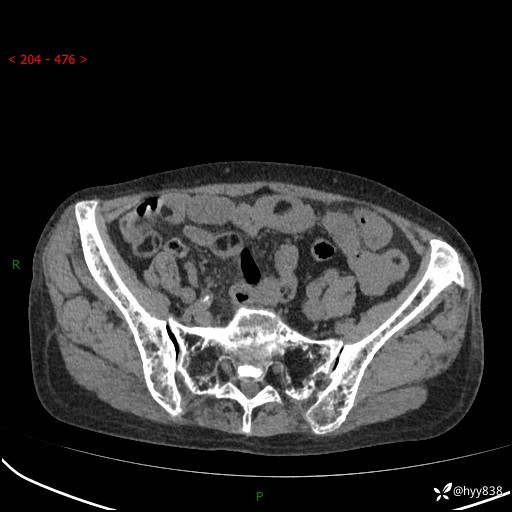

全腹部CT平扫